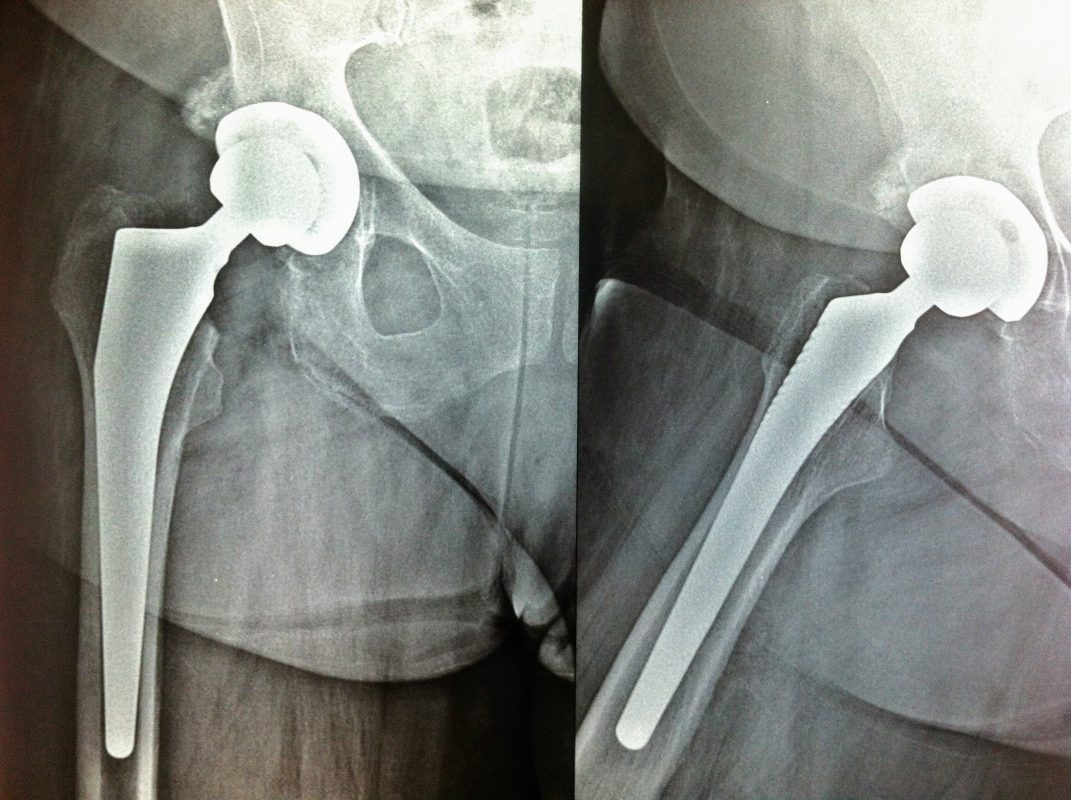

Σε αυτό το σημείο η Αρθροπλαστική Ισχίου αποτελεί μονόδρομο.

Παραδοσιακά οι αρθροπλαστικές ισχίου αποτελούνται από μια μεταλλική μπάλα – σφαίρα τοποθετημένη σε μια πλαστική κοιλότητα (κοτυλιαία πρόθεση).

Η πλαστική επιφάνεια στήριξης φθείρεται με την πάροδο του χρόνο, με ρυθμό μάλλον σχετιζόμενο με το επίπεδο δραστηριότητας του ατόμου. Αυτό έχει σαν επακόλουθο νεότεροι ασθενείς με μεγαλύτερο προσδόκιμο ζωής να έχουν αυξημένο ρίσκο αναγκαιότητας δεύτερης αρθροπλαστικής ισχίου (αναθεώρησης – Revision) επέμβαση που είναι πολυπλοκότερη και υπόκεινται σε υψηλότερο κίνδυνο επιπλοκών. Βάση των ανωτέρω, ιστορικά, η αρθροπλαστική ισχίου σπανίως εφαρμοζόταν σε ασθενείς κάτω των 60 ετών.

Χάρη στα νέα τεχνολογικά επιτεύγματα έχουν παραχθεί επιφάνειες στήριξης που ανταποκρίνονται σε μεγαλύτερα επίπεδα δραστηριότητας και αναμένεται να έχουν μεγαλύτερη διάρκεια ζωής. Αυτές οι καινούριες επιφάνειες στήριξης είναι συνήθως μέταλλο πάνω σε ειδικό σκληρότερο πλαστικό ή κεραμικό πάνω σε κεραμικό. Ως εκ τούτου, είναι τώρα πολύ πιο σύνηθες, νεότεροι ασθενείς να χειρουργούνται καθώς η πλειονότητα αυτών, που η αρθρίτιδα τους προκαλεί αφόρητους πόνους, επιλέγουν να έχουν ποιότητα ζωής από το να ζουν με τον πόνο.

Η αρθροπλαστική ισχίου αποτελεί μια αποτελεσματική επέμβαση αποκατάστασης και πρέπει να εφαρμόζεται μόνο όταν οι ασθενείς δεν είναι σε θέση να αντέξουν άλλο τον πόνο και την ανικανότητα και εφόσον τα πλεονεκτήματα καθώς και οι πιθανοί κίνδυνοι της μεθόδου έχουν εξηγηθεί πλήρως από το χειρουργό και έχουν κατανοηθεί από τον ασθενή.